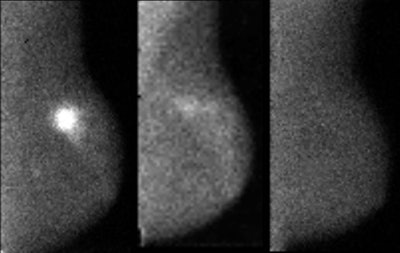

A 51-year-old patient diagnosed with triple-negative, stage II invasive ductal carcinoma measuring 3.5 cm at greatest extent. The image at left is MBI performed prior to beginning neoadjuvant chemotherapy. The middle MBI image was taken three weeks after initiation of chemotherapy (Taxol and carboplatin) and shows near-complete interval resolution of tracer uptake within the tumors, indicating good imaging response to chemotherapy. The MBI image at right was acquired after four months of chemotherapy and is negative, indicating complete response. At surgery, no residual disease was found.